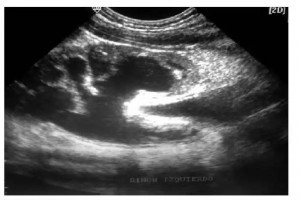

Diplomados en Ultrasonografía